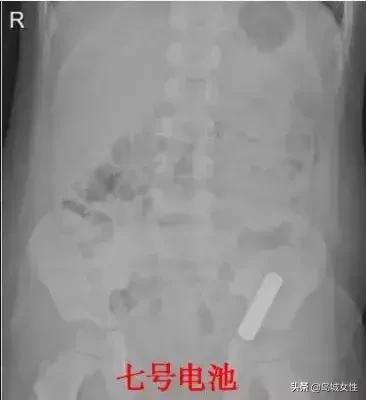

果核、扣子、硬币、别针、发卡、电池等等,这还都是常见的。

戒指、耳钉、干电池、绣花针、磁力珠、小木棒、拉链、螺丝钉……这些都是比较罕见的。

对于有毒害风险、尖锐物品。

如电池、针状物、螺钉等,还有造成消化道梗阻或长时间无法经排便排出的无毒害风险的异物。

则需要通过胃肠镜或腹腔镜等手术取出。